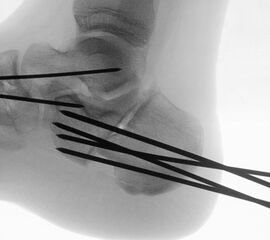

Liegt eine stark subduktische 5. Zehenposition vor, fräsen wir bevorzugt in der Kramertechnik für eine maximale Korrektur und Setzen für zwei bis drei Wochen einen intramedullären Draht nach proximal durch die Osteotomie (Abb. 27).

Abb. 27 a-d: Radiologische Darstellung intraoperativ (a) und vor dem Entfernen des Drahtes einer kompletten Schaftosteotomie mit intramedullärem Draht stabilisiert (b). Die Osteotomie wird minimalinvasiv durchgeführt und der Draht nach der Spülung über den gleichen Hautschnitt einfach in den Schaft hineingeschoben und die Osteotomie darüber stabilisiert. Das Köpfchen kann anschließend je nach Bedarf plantarisiert oder extendiert werden. Radiologische Verlaufskontrolle vor Entfernung des Drahtes (c-d).